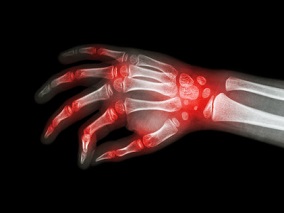

症状性手关节炎:泼尼松龙10mg 6周治疗安全有效

1小时条评论手骨关节炎有效治疗选择较少。2019年11月,发表在《Lancet》的一项研究显示,对于具有炎症体征的疼痛性手关节炎患者,泼尼松龙10mg治疗6周是一种有效和安全的治疗方案。 背景:手骨关节炎是一种常见的关节疾病,疾病负担较高,有效治疗选择较少,不能满足医疗需求。...